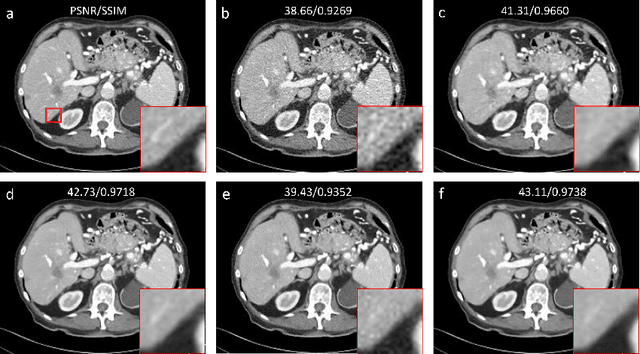

Low-dose computed tomography (LDCT) is an important topic in the field of radiology over the past decades. LDCT reduces ionizing radiation-induced patient health risks but it also results in a low signal-to-noise ratio (SNR) and a potential compromise in the diagnostic performance. In this paper, to improve the LDCT denoising performance, we introduce the conditional denoising diffusion probabilistic model (DDPM) and show encouraging results with a high computational efficiency. Specifically, given the high sampling cost of the original DDPM model, we adapt the fast ordinary differential equation (ODE) solver for a much-improved sampling efficiency. The experiments show that the accelerated DDPM can achieve 20x speedup without compromising image quality.